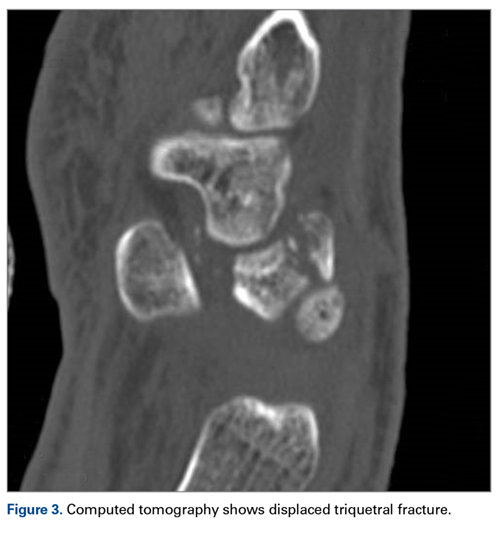

Later, however, the hand surgery team evaluated the radiograph as well as computed tomography (CT) scans and found a translunate, transradial, transtriquetral, transtrapezoid perilunate dislocation of the wrist with multiple metacarpal neck fractures ( Figures 1-5 ).The next day, with the patient under general anesthesia, an attempt to reduce the perilunate dislocation by manipulation was unsuccessful. Open reduction and internal fixation (ORIF) were performed through a dorsal approach; the perilunate dislocation was reduced and stabilized with lunocapitate 1.2-mm Kirschner wire (K-wire). The scapholunate and lunotriquetral ligaments were found to be intact, and the significantly displaced triquetral fracture was treated with internal fixation involving 2 minifragment screws ( Figure 6 ).

Our patient’s associated multiple metacarpal neck fractures can be explained by the peculiar double-impact injury with initial axial loading across the hyperextended metacarpophalangeal joint, followed by axial loading across the hyperextended and ulnar-deviated wrist, causing greater arc perilunate fracture-dislocation. The mechanism of lunate injury in this case seems to be longitudinal impaction of the capitate shearing against the volar lunate in the axial plane causing a volar lip fracture (Teisen type I), and this may be accentuated by tension in the volar radiolunate ligament. 6,7 Associated triquetral fracture in perilunate dislocation is well described in the literature. 6 However, the trapezoid fracture in our case implies a very atypical pattern of force transmission with the arc probably passing more distally through the trapezoid laterally and the triquetrum medially.

The goal in the treatment of perilunate dislocation with multiple carpal fractures is anatomical reduction and restoration of carpal alignment—which frequently require ORIF, though acute salvage procedures like proximal row carpectomy may be considered in irreparable fractures with extensive ligament injuries. 9 For open reduction, the approach can be dorsal, volar, or a combination. The approach in our patient’s case was dorsal. His triquetral fracture, his only displaced fracture, was treated with internal fixation. All other fractures were nondisplaced, stable, and did not warrant internal fixation.